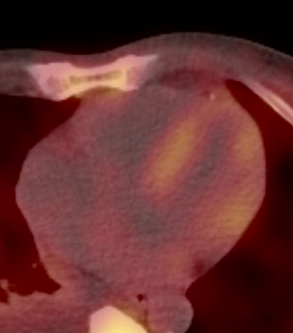

A 72-year-old man with atrial fibrillation and spontaneous bicep rupture presents as a referral to clinic for a 2-year history of progressively worsening dyspnea. A prior cardiac magnetic resonance showed subendocardial LGE throughout the left ventricle, with elevated T1 values and LVEF 25%. Prior coronary angiography with no coronary disease. Subsequently, a 99mTc HDP scan showed II/III in myocardial radiotracer uptake concerning for transthyretin cardiac amyloidosis (ATTR-CA) (Fig.1). Physical examination was notable for a BP of 93/59mmHg. JVP 16cmH20 with HJR. Heart had an irregularly irregular rate and rhythm, no murmurs. 1+ edema to the mid shins bilaterally. ECG low voltage and atrial fibrillation. Labs notable for Cr 1.17g/dL, NT-proBNP 4,872pg/mL. Serum free light chain assay with κ light chain 11.03mg/L and λ light chain 2080.7mg/L, for a κ/λ ratio of 0.01. The 24-hour urine sample with a free λ light chain excretion rate of 356.50 mg/24 hours. Bone marrow biopsy demonstrated 10% λ restricted plasma cell neoplasm with free λ/κ ratio of 188, meeting criteria for multiple myeloma. An endomyocardial biopsy with Congo red showed apple green birefringence and typing by mass spectrometry consistent with ATTR-CA (Fig. 2). Gene sequencing revealed his TTR gene was wild-type. Biopsy of the kidney with Congo red stain was focally positive for λ amyloid consistent with systemic AL amyloidosis (Fig. 3). He completed 6 cycles of cyclophosphamide, bortezomib, dexamethasone and daratumumb with a very good hematologic partial response. For his ATTR-CA, he was initiated on acoramidis, spironolactone, and empagliflozin with improvement in his symptoms and cardiac biomarkers over the following months.